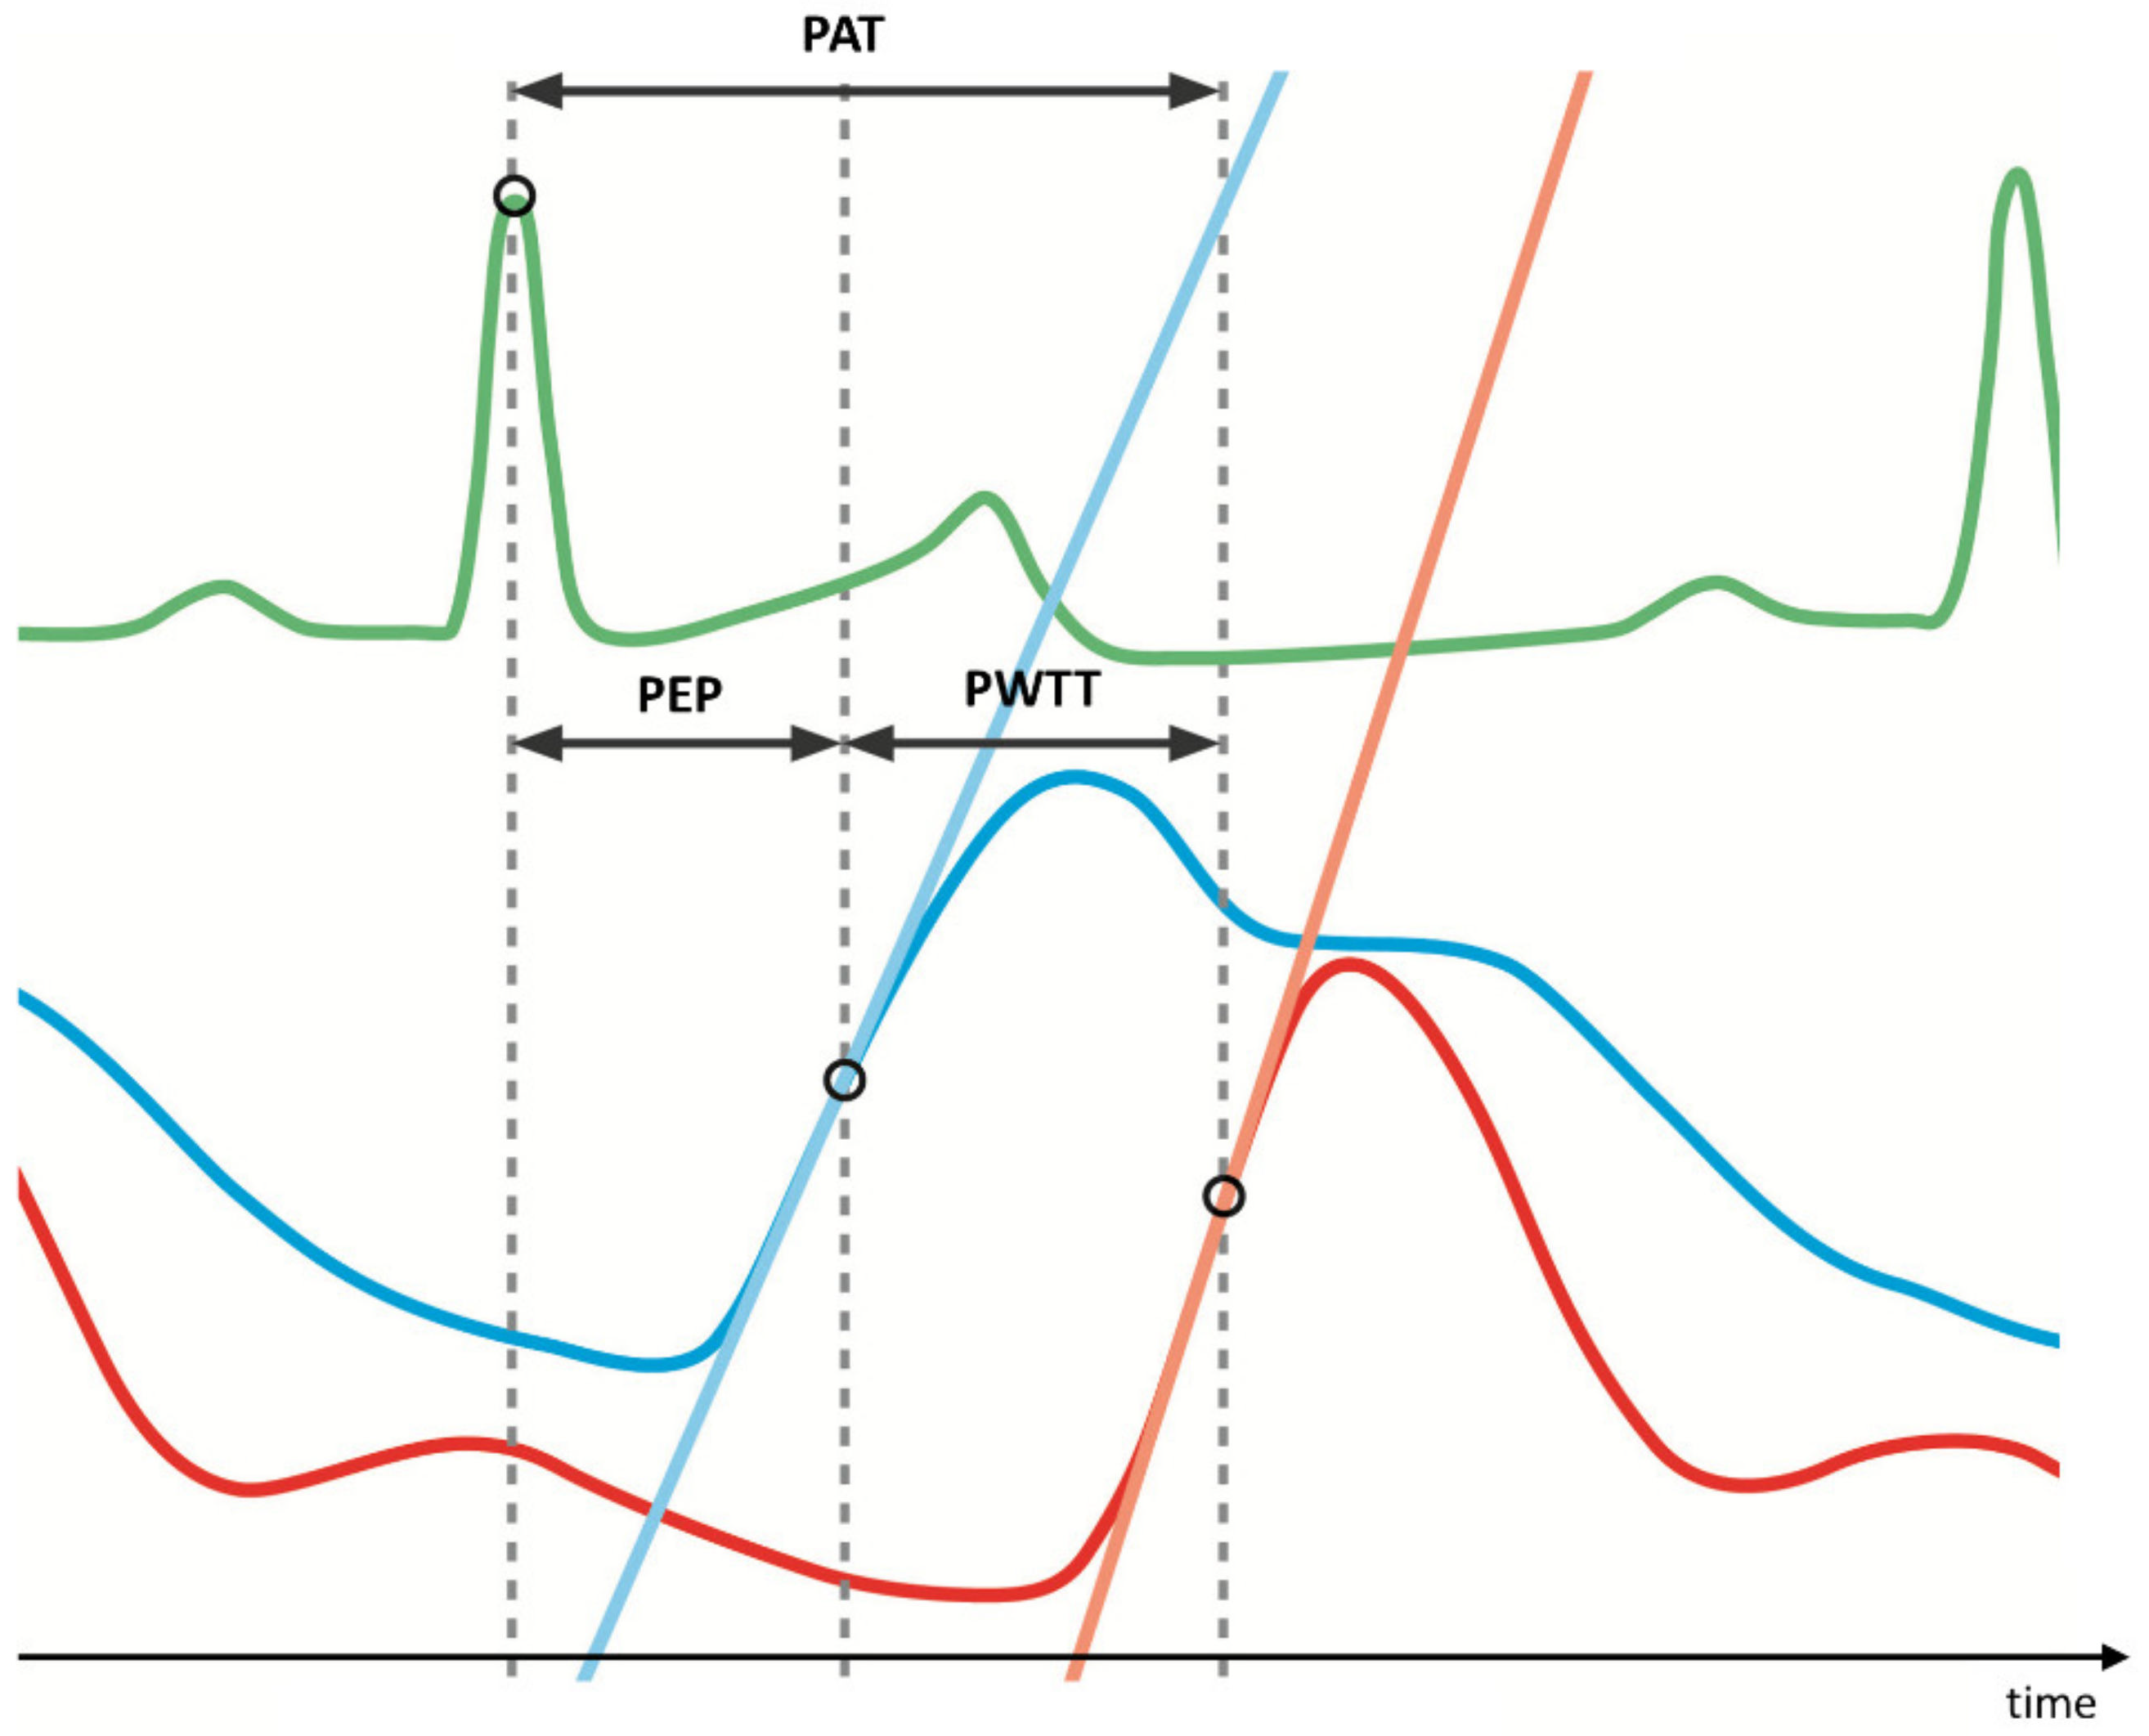

:1. Introduction

2. Materials and Methods

2.4. Data Acquisition and Processing